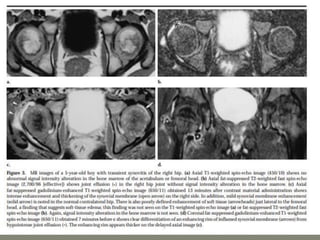

MRI- both tenosynovities and septic arthritis show

T1 hypo T2 /STIR joint effusion

Contrast enhanced image [T1+C]-

Rim of enhancing hypertrophic synovial membrane

differentiated by hypo intense joint effusion

MRI-

1]septic arthritis show signal intensity alteration in the

bone marrow of affected hip joint

2] In transient synovities cases show no such altered

signal entity in bone marrow

T1- poorly defined low signal intesity

T2-/STIR: hyperintese

Contrast study : show enhancment

MRI- both tenosynovitiesand septic arthritis show T1 hypo T2 /STIR joint effusion Contrast enhanced image [T1+C]- Rim of enhancing hypertrophic synovial membrane differentiated by hypo intense joint effusion

• 54.

MRI- 1]septic arthritis showsignal intensity alteration in the bone marrow of affected hip joint 2] In transient synovities cases show no such altered signal entity in bone marrow T1- poorly defined low signal intesity T2-/STIR: hyperintese Contrast study : show enhancment